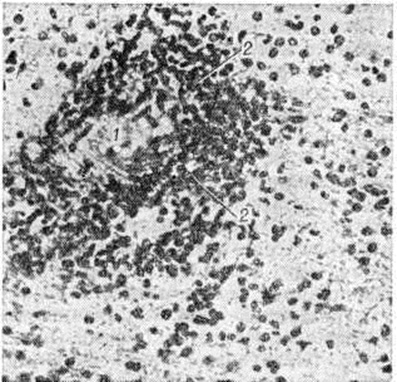

Рис. 2.

Микропрепарат ткани белого вещества мозга больного, умершего от геморрагического лейкоэнцефалита: стенка кровеносного сосуда (1) инфильтрирована и окружающая нервная ткань пропитана полиморфно-ядерными лейкоцитами (2).

Гистологический картина характеризуется диффузной подострой воспалительной реакцией с периваскулярной инфильтрацией лимфоцитами и плазмоцитами и очаговой демиелинизацией (рисунок 2). Воспалительные изменения преимущественно локализованы в белом веществе мозга, иногда в коре, подкорковых ганглиях, мозговых оболочках. Разрушается нормально сформированный миелин (миелинокластический тип поражения). Степень демиелинизации и деструкции нервной ткани варьирует в различных очагах. Отдельные мелкие очаги могут сливаться. У краёв очага демиелинизации олигодендроциты увеличены, содержат амфофильные включения, в более поражённых участках они полностью исчезают. Кроме того, встречается много больших причудливой формы астроцитов с гиперхроматическими многодольчатыми или несколькими ядрами. Аксоны остаются относительно сохранными на ранних стадиях процесса, позднее в них могут быть дистрофические изменения. Нейроны коры полушарий большого мозга могут содержать включения двух типов: сферические частицы диаметром 30—40 микрометров и продолговатые, или тубулярные, структуры несколько меньшего диаметра. Включения чаще встречаются при небольшой длительности заболевания. Гистохимический исследования обнаруживают во включениях большое количество белка. В большинстве случаев находят пролиферативную реакцию глии. Глиоз может быть мелкоузелковый или в виде крупных очагов (псевдоопухоль). Диффузное разрастание волокнистой глии приводит иногда к уплотнению мозгового вещества, так что мозг на разрезе имеет хрящевидную консистенцию. Стенки артерий и вен утолщены, с избытком ретикулярных волокон в адвентиции.

Острый геморрагический лейкоэнцефалит. По клинические, и патоморфологический признакам эта форма Лейкоэнцефалит сходна с вирусными и поствакцинальными энцефалитами. При патологоанатомическом исследовании выявляют отёк мозга, на срезах в веществе мозга — большие очаги мягкой розовато-серой или желтоватой окраски с множественными точечными кровоизлияниями. Гисто л. картина характеризуется фибринозным некрозом стенок мелких сосудов, в основном венул, окружённых экссудатом фибрина, воспалительными клетками и кольцевидными геморрагическими зонами. В этих же периваскулярных зонах — демиелинизация с умеренной или выраженной деструкцией аксонов. На самых ранних стадиях периваскулярные инфильтраты представлены главным образом нейтрофилами, однако в более старых очагах находят много лимфоцитов и плазмоцитов.